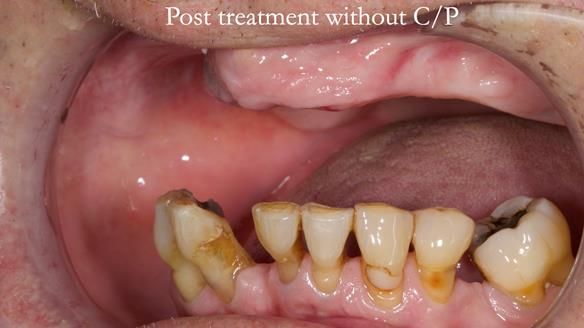

Welcome to my Newsletter 54 showing the making and fitting of dentures (a complete upper metal reinforced denture, a lower immediate partial denture and a definitive Scandinavian designed, metal based lower partial denture) for David, a 75 -year-old man. The full protocol workflow is presented including the use of dentate photographs to mimic his natural teeth.

- Current complete upper denture had many technical problems. Poor retention, support, stability and tissue fit.

- Missing teeth on the lower right side. This makes the upper denture tip when chewing and biting.

- The remaining lower 9 teeth had periodontal disease. Syed Abad, Specialist in Periodontics at the practice managed it.

Interestingly we found that the upper complete denture when finished and fitted didn’t have good enough retention for David’s satisfaction. It was relined by adding compound to the buccal flanges – to almost overextend into the sulcus to ‘create’ a sulcus, followed by using a light bodied silicone impression material. This improved the function of the C/-considerably. A lower Scandinavian hygienically designed lower RPD was also provided which helped with occlusal stability and reseating the upper denture – further improving the fit.